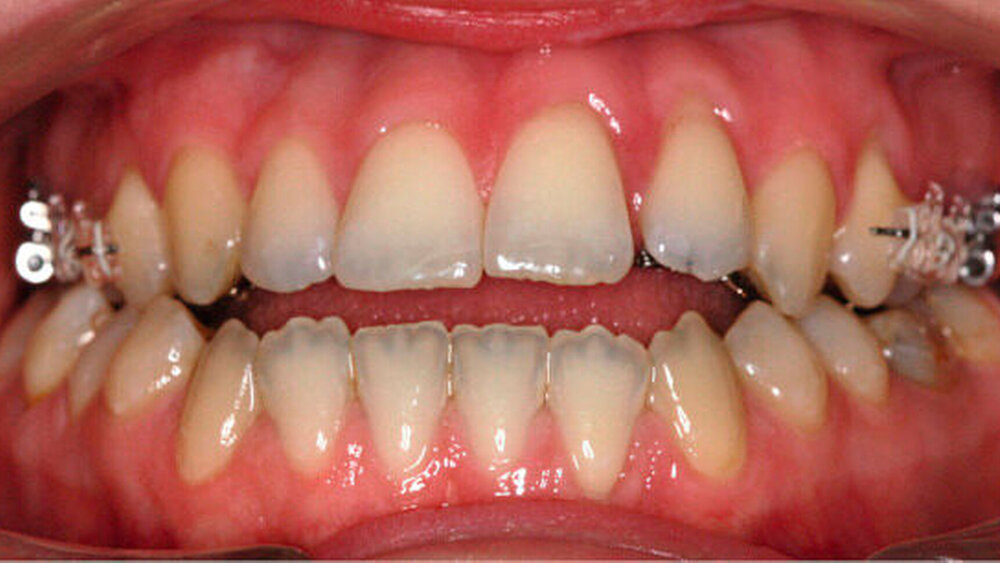

Anfangs wurde bei der Patientin eine transversale Expansion von etwa 5 mm mittels konventioneller GNE (Abbildung 3a) durchgeführt. Nach sechsmonatiger Retention durch Belassen der GNE-Apparatur konnte die individualisierte linguale Apparatur (Incognito, 3M Unitek, TOP-Service für Lingualtechnik GmbH, Bad Essen) eingesetzt werden (Abbildung 3b).

Die Bogensequenz bestand aus folgenden Bogenstärken: 0.14 Nickel-Titan (NiTi), 0.16 NiTi, 0.16 x 0.22 NiTi, 0.16 x 0.22 Stainless Steal (SS), 0.18 x 0.25 SS und einem 0.18.2 x 0.18.2 Titan-Molybdän-Alloy (TMA) für die postoperative Feineinstellung der Okklusion.

Entscheidend bei der präoperativen kieferorthopädischen Therapie war es, den Overbite offen zu halten und die negative sagittale Stufe durch Dekompensation der Incisivi-Position zu vergrößern, um die chirurgische Umstellung zu ermöglichen.